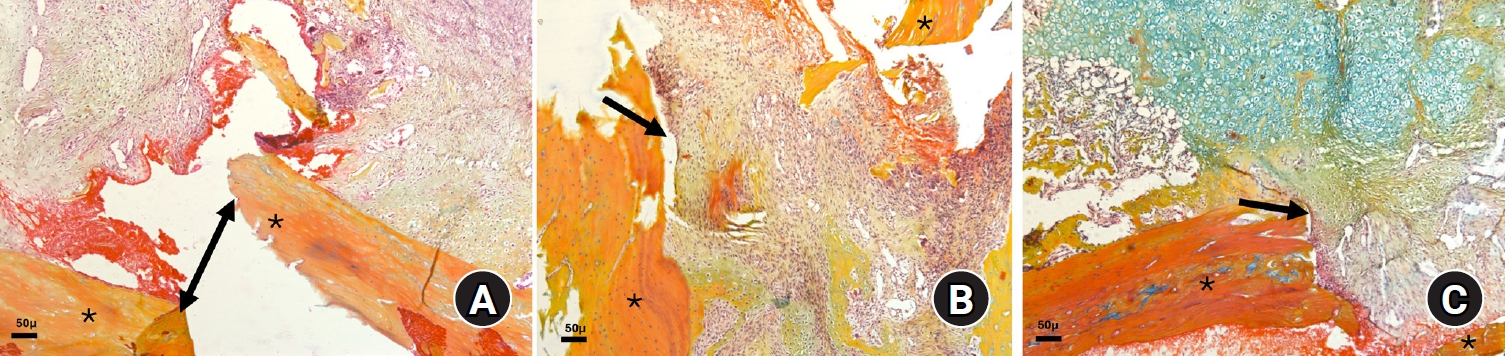

Fig. 3.

Photomicrographs of Alcian blue hematoxylin orange G (ABH/OG)-stained slides illustrating fractured bone edges (*) with callus formation at 2 weeks after fracture in the three animal groups: (A) diclofenac group, (B) celecoxib group, and (C) control group (magnification, ×50). Notably, in the control group, the fracture gap is filled with soft callus tissue (black arrow), unlike in the two experimental groups, where the gap is partially filled with granulation tissue (double-sided and black arrows in A and B, respectively). The bluish staining in C indicates the presence of more cartilaginous tissue.

Histological scoring at 2nd week

Among individual parameters, fibrosis scores were significantly lower in the NSAID-treated groups (P=0.03) indicating greater fibrous tissue at the fracture site. Pairwise comparison using Dunn’s post hoc test showed significant difference only between diclofenac group and controls (P=0.01). The overall healing scores were also found significantly lower in experimental animals (P=0.01) while pairwise comparison using Dunn’s post hoc test showed significant difference only between diclofenac group and controls (P=0.004) (Table 2, Fig. 3).

At the 7th week, newly formed bone was significantly greater in the control group compared with the experimental groups (P=0.01). Pairwise comparisons using Dunn’s post hoc test demonstrated a significant difference between the diclofenac and control groups (P=0.003). Bone defect scores were significantly lower in the diclofenac group (P=0.03) reflecting larger residual bone defects). Dunn’s post hoc analysis revealed a highly significant difference between the diclofenac group and controls (P=0.01), as well as borderline significance between diclofenac and celecoxib groups (P=0.05) (Fig. 4). Total healing scores were significantly lower in experimental animals (P=0.03), with pairwise comparisons showing significant differences between the diclofenac group and controls (P<0.001) and between diclofenac and celecoxib groups (P=0.03) (Table 2).